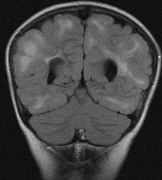

Mental retardation and seizures in TSC are often associated with benign CNS astrocytic hamartomas.131 On imaging, the cerebral lesions show three patterns:132

1. Superficial cortical sclerosis (parenchymal hamartoma) which distort the gyri. Microscopy shows large atypical fibrillary type astrocytes with few associated neurons and areas of calcification.133 The numerous abnormal glial processes and fibers make the tissue abnormally firm or “sclerotic” on palpation (Fig. 13).132

2. Subependymal nodules (SEN) are typically found along the lateral borders of the ventricles and parehncymal brain lesion (“cortical tubers”) (Figs. 14 and 15). Calcification in the first year of life is rare.132

On MRI imaging, the subependymal nodules and parenchymal brain lesions of infants (age ≤3 months) and adults show different signal characteristics. Infant CNS tubers are hyperintense on T1-weighted images and hypointense on T2-weighted images, which is the opposite of the pattern seen in adults.134 Malignant transformation of SEN occurs in about 10% to 15% of patients and the resultant subependymal giant cell astrocytoma accounts for 25% of premature deaths in TSC.135,136

Fig. 13. Tuberous Sclerosis Complex: “cortical sclerosis.” Numerous abnormal glial processes make the tissue abnormally firm or “sclerotic” on palpation.132

Fig. 14. Tuberous Sclerosis Complex: Sub-Ependymal nodules. These are typically found along the lateral borders of the ventricles.132